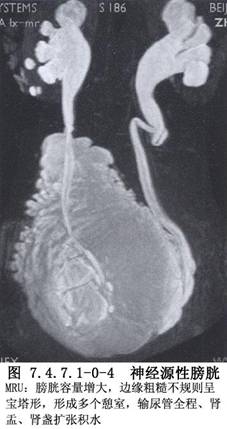

②確定神經源性排尿功能障礙類型的方法:通過全面的尿動力學檢查,包括膀胱測壓、壓力流率測定、尿道測壓、肌電圖及影像尿動力學檢查等,即可確定神經源性排尿功能障礙的類型(圖7.4.7.1-0-3,7.4.7.1-0-4)。